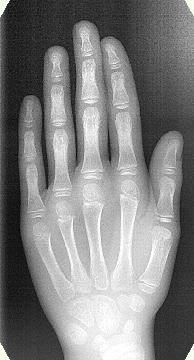

ภาพรังสีกระดูกข้อมือ

ทั้งการเปลี่ยนฟันและการเจริญพัฒนาของกระดูกขากรรไกรที่จะเกิดขึ้นนับว่า มีความสำคัญอย่างยิ่งต่อการวางแผนการรักษาทางทันตกรรมจัดฟันแบบที่ต้อง ใช้เวลารักษานานหลายปีและต้องคำนึงถึงการเจริญเติบโตพร้อมกันไปด้วย จากภาพรังสีกระดูกข้อมือจะสามารถทำให้กำหนดระยะการเจริญเติบโตของร่า งกายและพร้อมกันกับทำให้สามารถกำหนดระยะการเจริญพัฒนาของกระดูกข ากรรไกรได้ สำหรับการประเมินระดับการเจริญเติบโตของกะโหลกศีรษะและระดับการเจริ ญพัฒนาของผู้ป่วยนั้นถือว่าอายุกระดูก (สภาวะการเจริญเติบโตของโครงกระดูก) เป็นตัวบ่งที่แน่ชัดเชื่อถือได้มากที่สุด ส่วนอายุฟัน (สภาวะของฟันที่มีอยู่) ไม่เหมาะสมที่จะนำมาใช้เป็นตัวบอกสภาวะการเจริญพัฒนาของแต่ละบุคคล เนื่องจากการเจริญพัฒนาของฟันไม่สัมพันธ์กันกับการเจริญพัฒนาของโครงก ระดูก

ค่าผลการวิเคราะห์ภาพถ่ายรังสีมือสามารถใช้เป็นข้อมูลที่มีประโยชน์ต่อการกำ หนดเวลาเริ่มต้นรักษา แนวทางปฏิบัติการรักษาและระยะเวลาคงสภาพตามความจำเป็นได้ แต่ทว่าในเด็กวัยรุ่นจะถ่ายภาพกระดูกข้อมือก็ต่อเมื่อการเจริญพัฒนาของกระ ดูกขากรรไกรมีความสำคัญต่อผลสำเร็จในการรักษาเท่านั้น